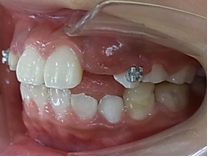

今回の開咬は将来、顔貌や顎の関節に悪影響を与えることがあり、外科矯正(顎切)になる確率が高い症例です。

矯正治療前 矯正治療後